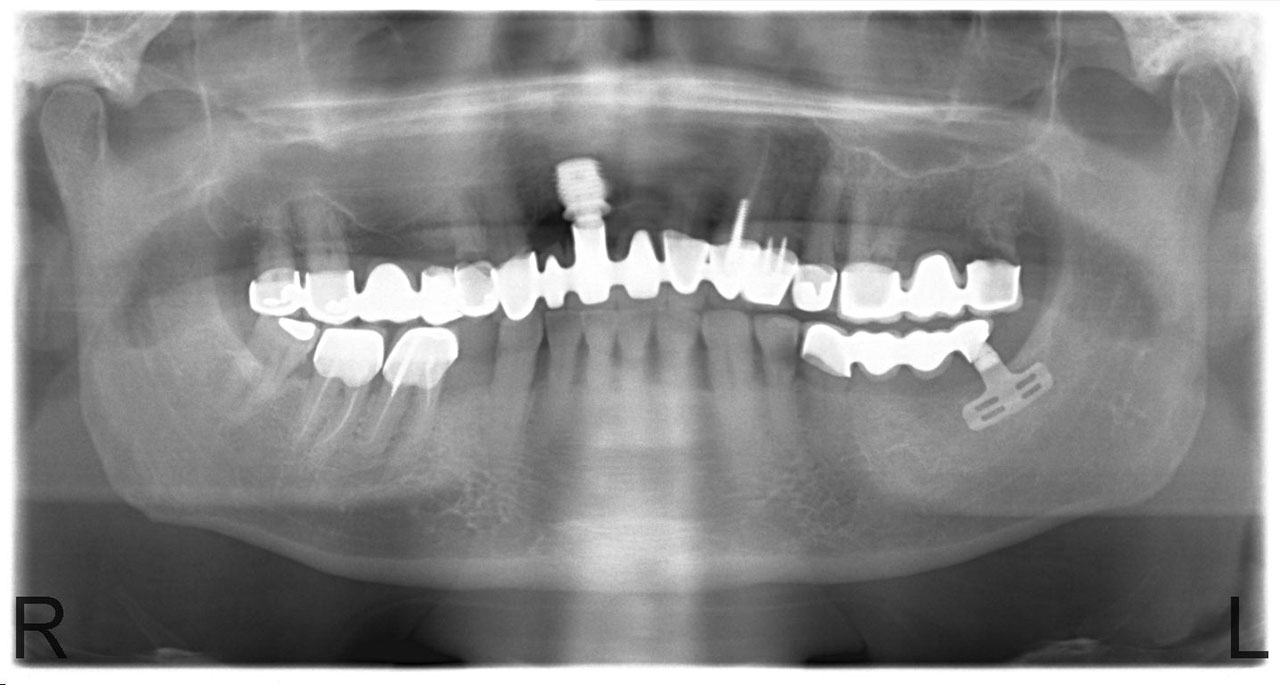

Impantáció előtt, súlyos fogágy pusztulás, gyulladás látható.

• esettanulmany-06

Impantátumok a végleges híddal.